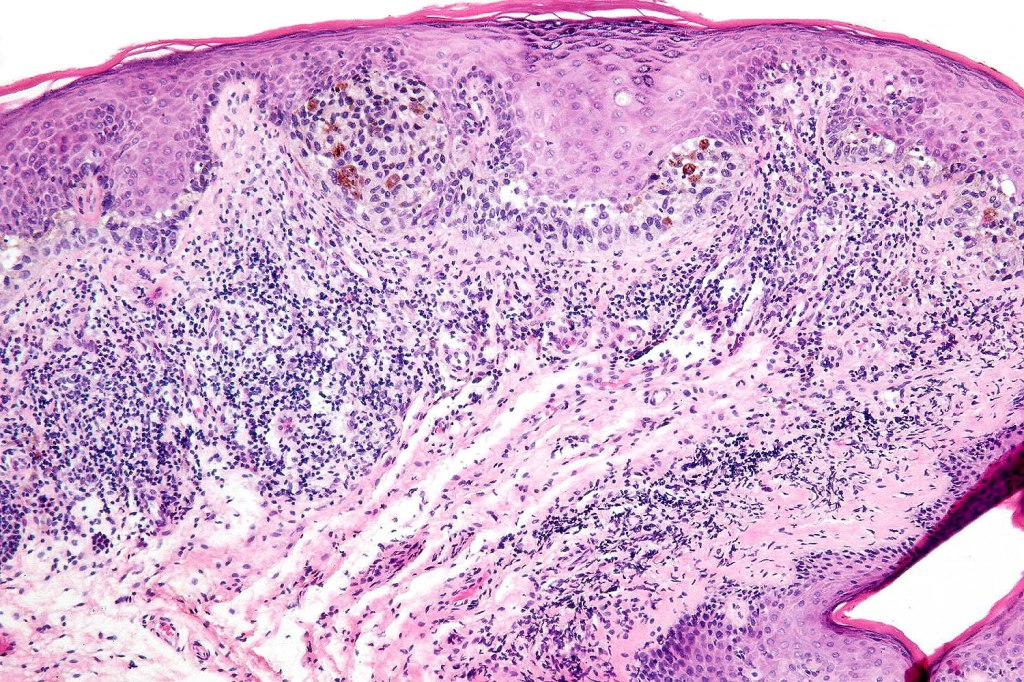

Histological features

•Junctional/compound

•Large dyscohesive nests with retraction artifact, not restricted to the tips of the epidermal ridges

•Heavy pigmentation (sometimes gray/green)

•Bridging common, often over multiple rete ridges

•Variable atypia (can be marked)

•Dermal fibrosis (sometimes lamellar)